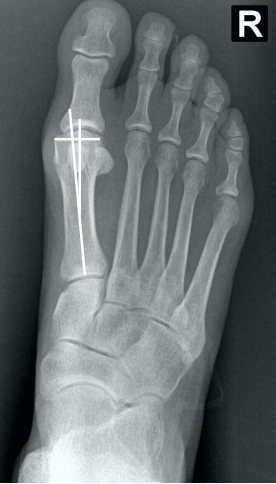

• Na avaliação radiográfica em AP com carga, quais os principais ângulos a serem traçados?

• Ângulo de valgismo do hálux (metatarsofalângico)

• Ângulo intermetatarsal (entre o 1° e 2° mtt)

• Ângulo de valgismo interfalângico do hálux

• Ângulo articular metatarsal distal (AAMD)

• Na radiografia em AP com carga, como é traçado o ângulo intermetatarsal?

• Ângulo entre o eixo longo do 1° e do 2° raio

• Normal → até 9°

• Leve → 9° a 12°

• Moderado → 13° a 15°

• Grave → > 16°

• Na radiografia em AP com carga, como é traçado o ângulo de valgismo do hálux (metatarsofalângico)?

• Ângulo entre o eixo longo do 1° mtt e o eixo longo da falange proximal

• Normal → até 15°

• Leve → < 25°

• Moderado → 25° a 40°

• Grave → > 40°

• Na radiografia em AP com carga, como é traçado o ângulo de valgismo interfalângico do hálux?

• Ângulo entre o eixo longo da falange proximal e o eixo longo da falange distal

• Normal → até 10°

• Na radiografia em AP com carga, como é traçado o ângulo articular metatarsal distal (AAMD)?

• Traça-se uma linha unindo os dois pontos mais largos da superfície articular do 1° mtt e outra linha perpendicular a esta

• Depois, traça-se uma linha no eixo longo do 1° mtt

• O ângulo entre as duas maiores retas → até 15°